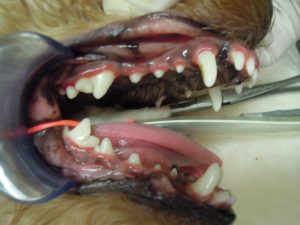

2.左側外観です。

3.まず、スケーリングをして口の中をきれいにしてから

4.プロービング検査で歯周ポケットの深さを測定して